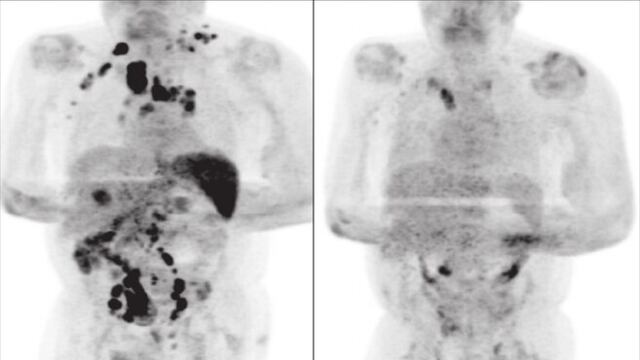

Los especialistas Sarah Challenor y David Tucker, declararon a la British Journal of Haemathology, que el paciente de 61 años había sido diagnosticado con cáncer por linfoma de Hodgkin en etapa 3, es decir, la enfermedad ya estaba en todo su cuerpo; sufría de graves bajas de peso, inflamación de los ganglios, y de problemas renales que trataba con diálisis.

Cuatro meses después, el paciente regresó al hospital a una consulta médica de rutina. Para sorpresa de sus doctores, el hombre mostró una mejoría evidente ante el cáncer: ya no estaban inflamados los ganglios.